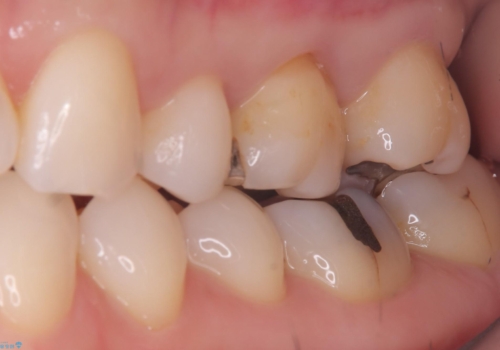

- 主訴:詰め物と歯の境目によごれがいつも溜まっている。フロスを通すと引っかかる。

保険適用のメタルインレーと歯質の境目が、歯質が欠けてしまったのか大きなくぼみ汚れが停滞しやすい状態になっていました。歯冠色材料でのやり替えを希望されたため、セラミックインレーでのやり替えとなりました。

左上6番に入っている保険適応のメタルインレーと歯質との境目(近心側室エリア)に不適部位を認め、そのくぼみに汚れが停滞しやすい状態となっていました。

適合性・審美性を考慮し、セラミックインレーでのやり替えとなりました。